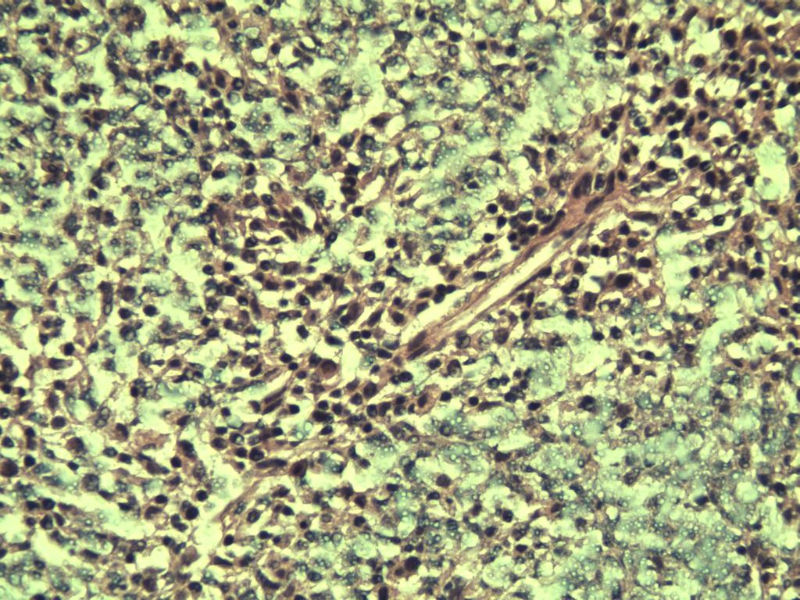

男,38岁,腹股沟 多枚淋巴结活检  直径 0.2-0.5 请各位老师看看 是什么 谢谢了!

"畏寒,发热咳嗽1年,加重伴腹部疼痛2月" 2月前患者感腹部疼痛不适伴大便呈稀大便,量不详,伴腰骶部疼痛,胸片:纵膈及右肺门多发性淋巴结肿大,进一步完善胸部CT:右肺及中叶病变,纵膈及肺门多发淋巴结肿大,结核性可能,脾脏增大,PPD(-),1个月来患者出现中上腹食欲不振,体重进行性消瘦,全身疲乏无力,3天前到医学院就诊,腹部B超:右肝囊肿,胆囊壁毛糙,脾大,胰周多个减弱回声,淋巴结不能除外,腹水,血常规示:WBC16.36x109 /L,N%14.25%,RBC2.63x1012/L ,HGB 66g/L 。右侧腋窝及腹股沟可扪及多枚淋巴结,压痛,无明显粘连。

腹股沟 多枚淋巴结活检图1

副皮质区增生,纤维化显著,细胞呈多形性,有一些多核巨细胞及一些异型细胞,病理性核分裂易见,胞浆红染,散在的小淋巴细胞,T细胞淋巴瘤不能除外,树突细胞肉瘤等鉴别。免疫标记。CD21、CD3、CD5、CD10、CD20、CD79a、PD1、CD68、CXCL13、KI-67、CD68、CD163等,据切片选择。不知对否。

淋巴结正常结构破坏,可见大的异型细胞,上皮样或梭形,恶性肿瘤,依据病史,首先考虑淋巴造血系统疾病,大中小细胞混杂,大细胞多,形态多样,可见多核瘤细胞,除以上考虑外需鉴别间变大、组织细胞肉瘤、指状突/树突细胞肿瘤、HL等,还需排除肉瘤或癌转移,尽管病人年轻,加上ALK、CK、S-100、CD1a。